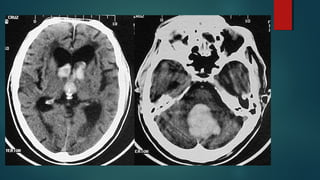

Este documento es el programa para un taller de imágenes del curso de emergencia 2015 impartido por el Dr. Víctor Delgado. El taller se centra en el uso de imágenes médicas para el diagnóstico y tratamiento de pacientes en coma traumático según la base de datos de Marshall. El Dr. Delgado es el único instructor repetido a lo largo del documento.